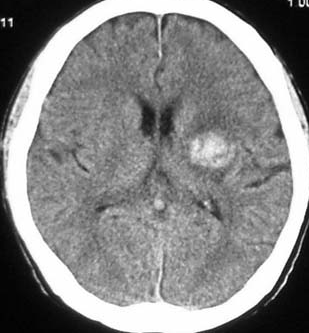

左は脳出血のCTです。海綿状血管腫からの出血を疑ったので造影のMRI(右の写真)をしました。血腫の周りに細い線がたくさん見えます。これが静脈奇形(静脈性血管腫)です。脳血管撮影DSAをしなくてもこの合併はわかるのです。この静脈奇形を手術で傷つけるとかなり広い範囲で脳梗塞がおきる可能性があります。